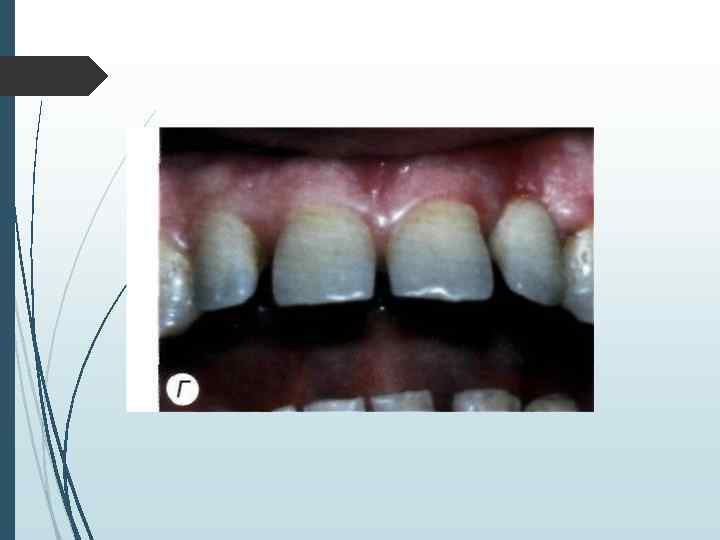

При осмотре полости рта необходимо определить: - вид адентии; - состояние оставшихся зубов; - протяжённость дефектов зубных рядов; - состояние гигиены полости рта; - прикус; - межальвеолярную высоту в области де фектов зубных рядов; - состояние слизистой оболочки полости рта; - глубину преддверия полости рта; - линию улыбки.